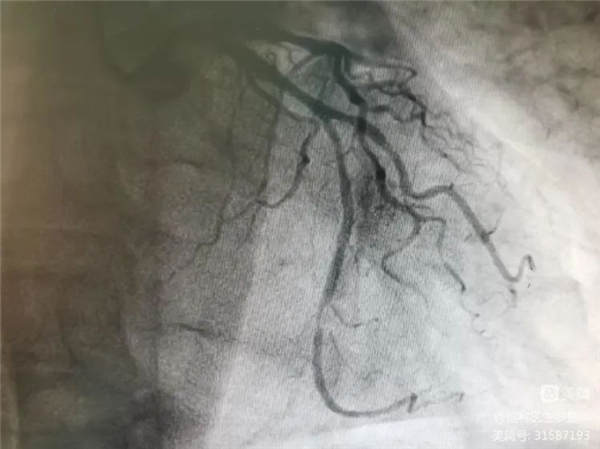

沈桂冬主任團隊正在為患者行PCI術

冠脈造影證實左旋支重度狹窄